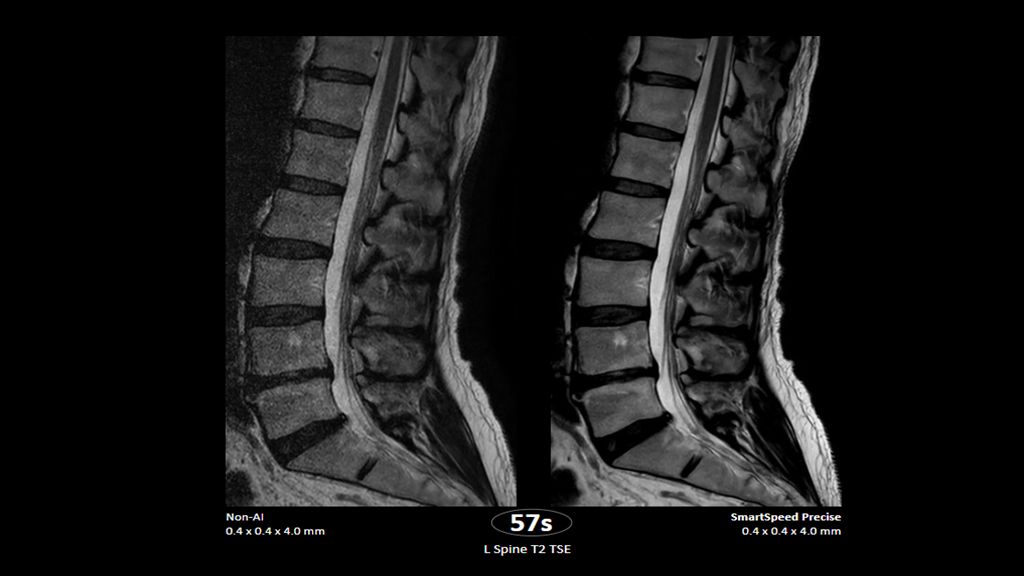

1. Compared to SENSE imaging, with no loss in image quality.

2. Reconstruction technology Compared to conventional (SENSE/ Compressed SENSE, SmartSpeed AI) imaging. Sharpness was evaluated with phantom scanning.